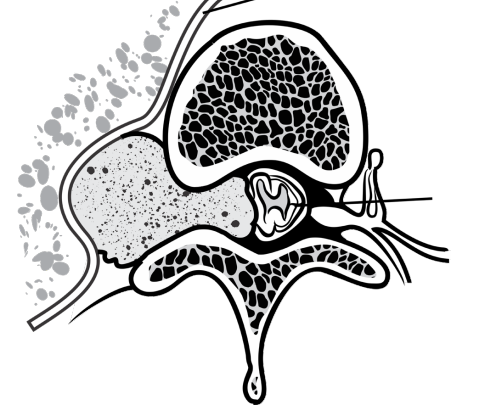

1 – Timo;  2 – Traqueia/ligamentos tireotímicos; 3 – Nervo frênico; 4 – Nervo vago/região inicial da artéria braquiocefálica esquerda; 5 – Artéria pulmonar esquerda; 6 – Veias tímicas; 7 – Saco pericárdico; 8 – Diafragma. Fonte: Acervo de Ilustrações do Grupo MedCof.